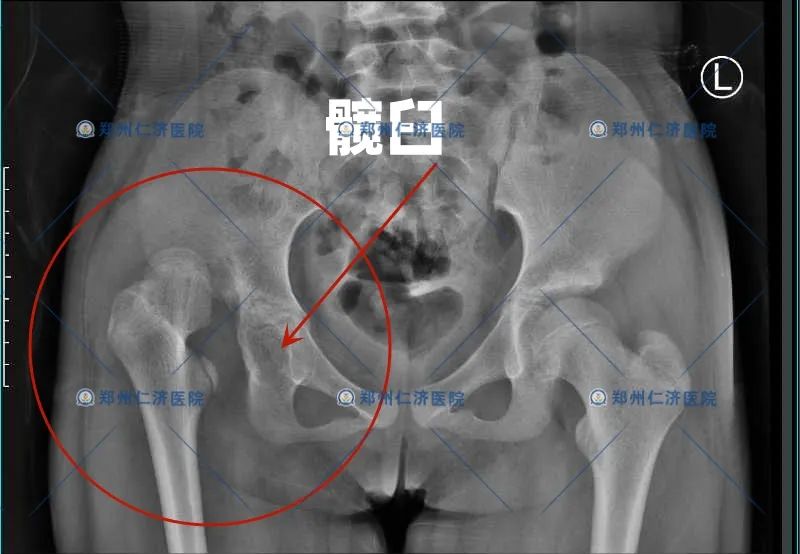

发现:优优的髋关节 相对严重

整个股骨头向上高脱、完全脱离了髋臼

另外,原本发育就不好的髋臼

已经没有了基本的外形

就像一顶被搁在远处的

“破了的草帽”

术前/术后2个多月 对比

髋臼贴合的“戴在”股骨头上